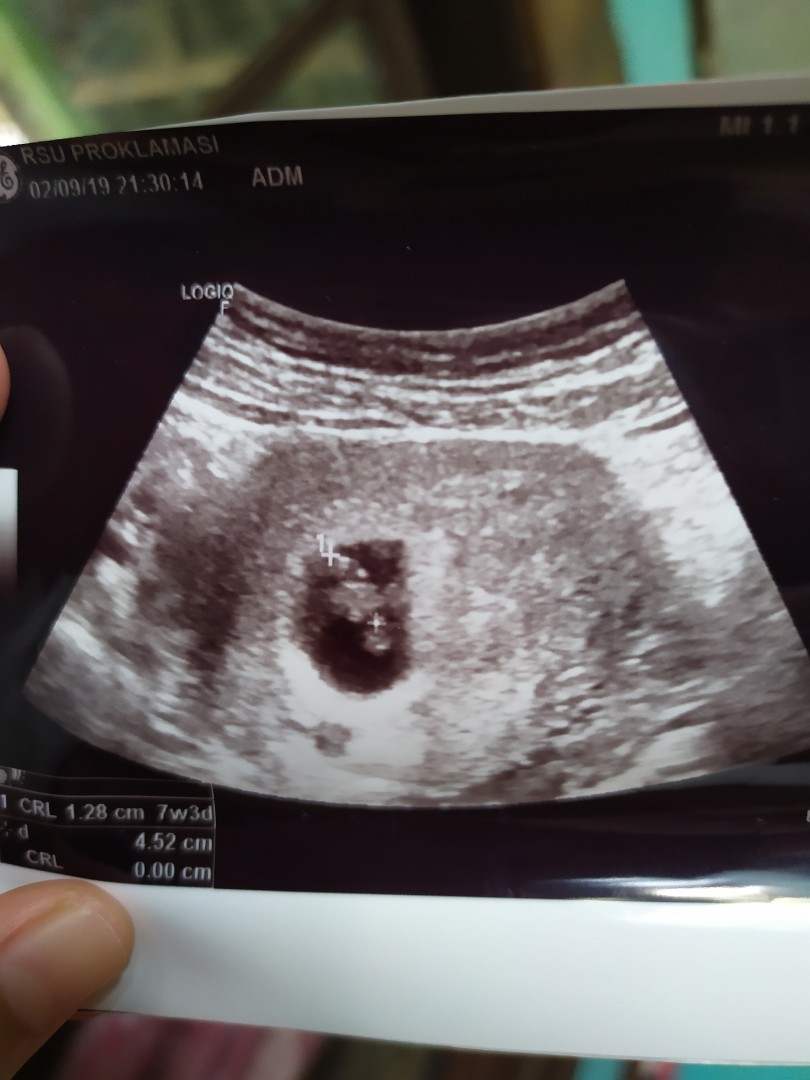

7w3d

Assalamu'alaikum bunda2. Mf mau tanya usia kandungan saya 7w3d apa normal USG blm keliatan janin nya baru keliatan kantung nya aja? Bunda2 usia kandungan brpa udh keliatan janin nya?